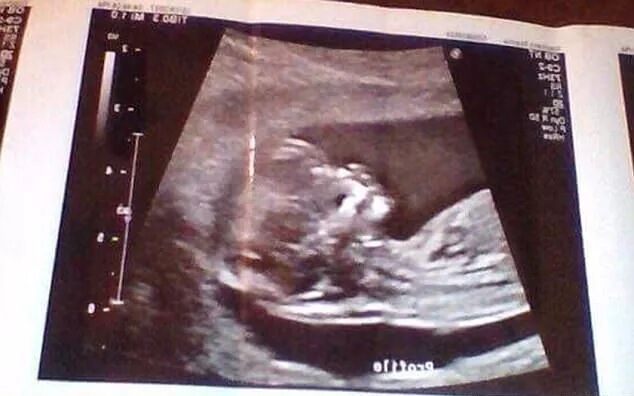

一位即将成为妈妈的女生在一系列的自拍照中展现了她小小的平肚子。

18岁的Reanna Stephens预计4月会生下她的儿子,但她很苗条,不认识她的人都怀疑她是否真的怀孕。